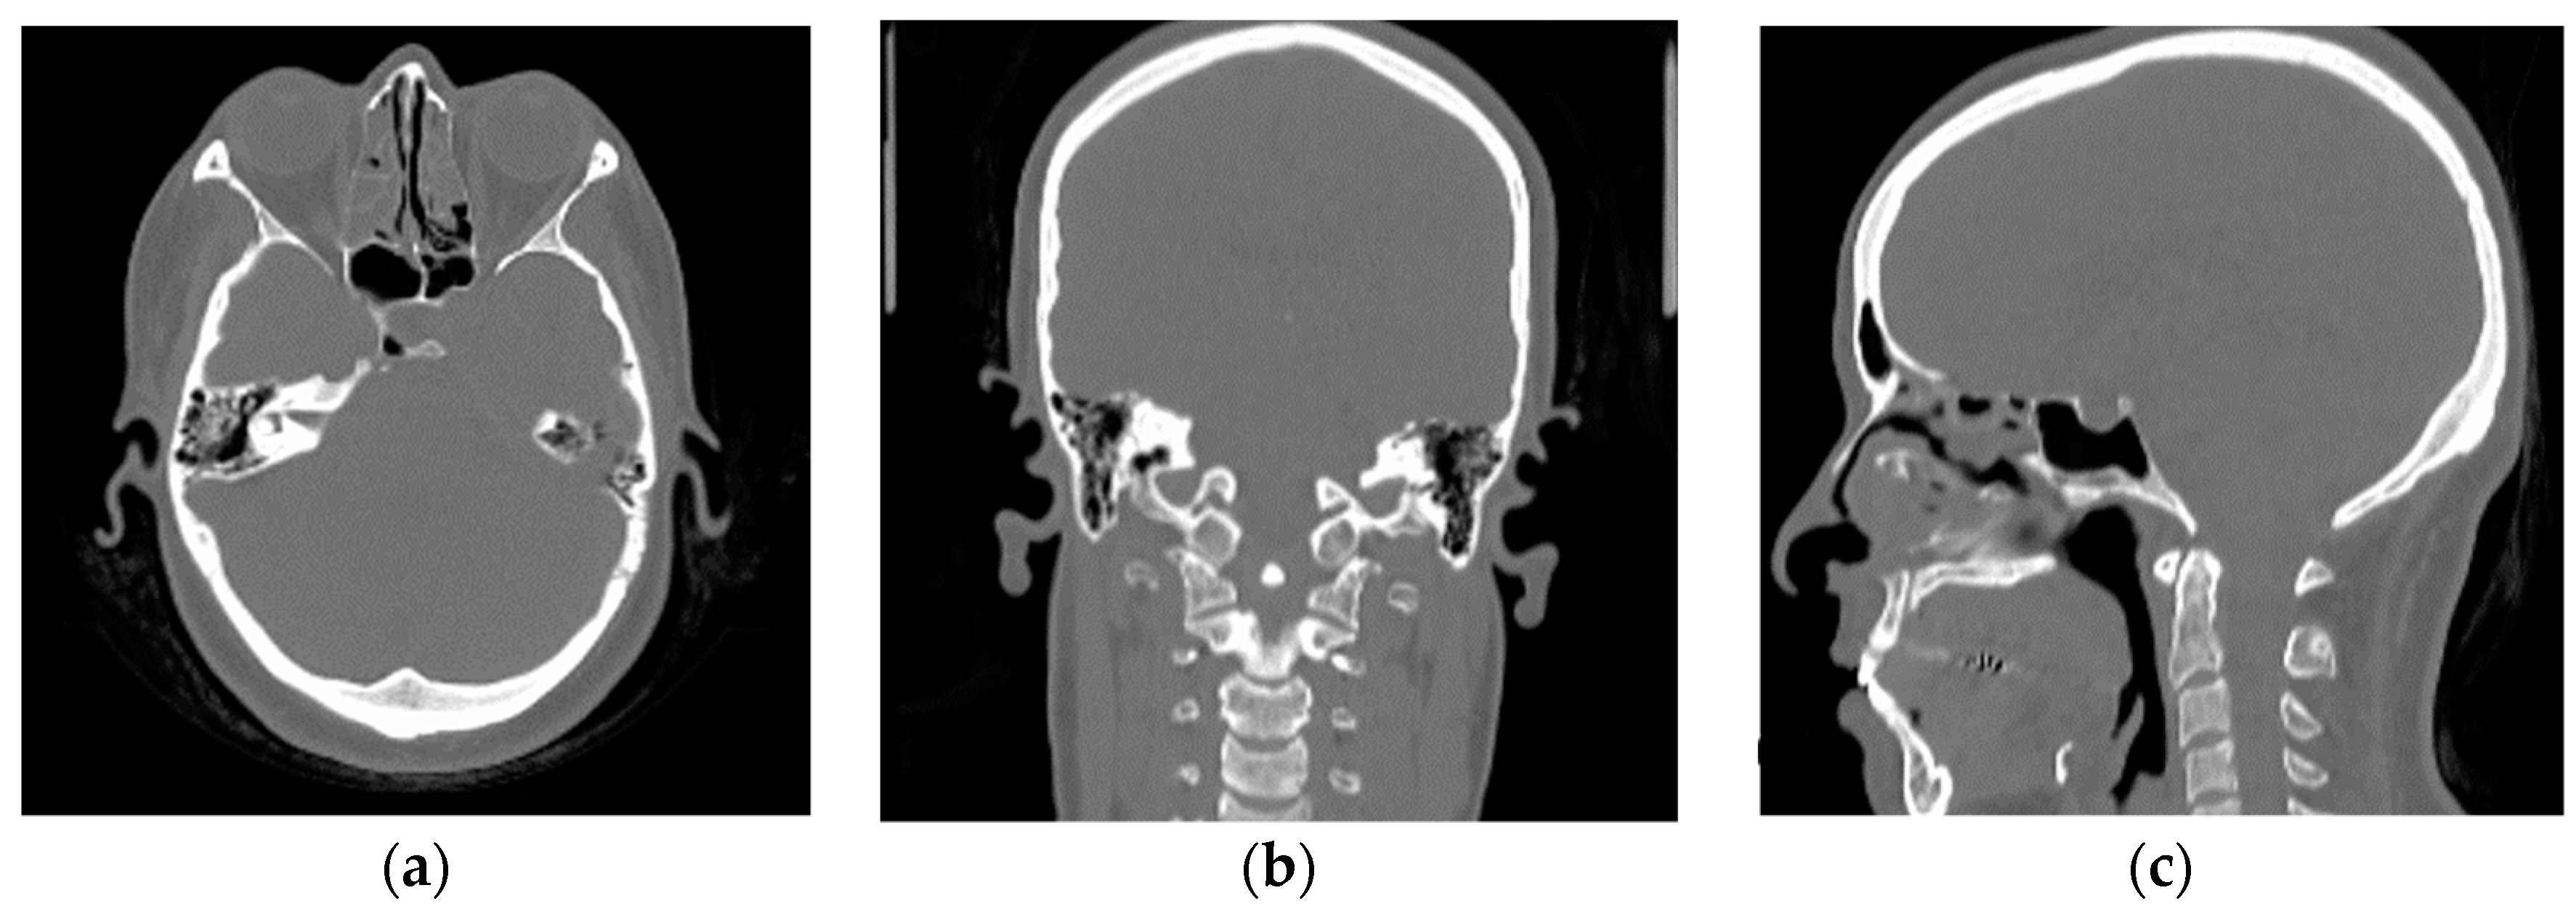

2.2. Magnetic Resonance-Computerized Tomography (MR-CT) Datasets

2.2.1. Training Dataset

2.2.2. Validation Dataset